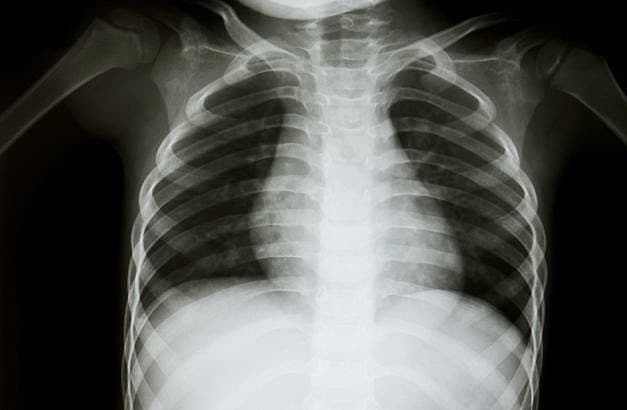

Astmadødelighed stagnerer på verdensplan

Analyse af mortalitetsdata fra 46 lande viser, at efter et fald i perioden 1993-2006 er dødeligheden af astma ikke faldet yderligere i de seneste år.

Langt de fleste astmadødsfald betragtes som potentielt forebyggelige. I perioden 1960-1980 rapporterede en række lande ophobede tilfælde af astmadødsfald. Man talte ligefrem om ”epidemier af astmadødsfald” og tilskrev årsagen et overforbrug af korttidsvirkende inhalerede beta-2-agonister uden samtidig brug af inhalationssteroid. Ny artikel opgør internationale tendenser i dødelighed af astma blandt 5-34-årige. Den konkluderer, at den faldende tendens i dødelighed, der blev observeret i perioden 1993-2006, ikke er fortsat i perioden 2006-2012. Foruden at pege på, at en bedre implementering af de kliniske retningslinjer for behandling og opfølgning utvivlsomt vil forhindre nogle af dødsfaldene, efterlyser forfatterne nye strategier, hvis vi skal forhindre flere af disse potentielt forebyggelige dødsfald.

Professor Charlotte Suppli Ulrik, Hvidovre Hospital, kommenterer: »Sammenlignet med andre lande er dødeligheden af astma lav i Danmark, men også her er det vigtigt med tiltag, der yderligere kan reducere dødeligheden af en sygdom, der som udgangspunkt ikke burde være forbundet med betydende overdødelighed. Trods adgang til relevant medicin, primært inhalationssteroid, og implementering af kliniske retningslinjer har mange, ikke mindst yngre, danske patienter med astma, ringe sygdomskontrol. Tidligere undersøgelser af astmadødsfald har vist, at der oftest er tale om patienter med mild til moderat sygdom, hvorfor dødsfaldene burde kunne være undgået. Der er derfor generelt behov for tættere og mere struktureret opfølgning af patienter med astma, og herunder ikke mindst fokus på adhærens med den forebyggende behandling og justering af behandlingen i forhold til sværhedsgrad af sygdommen, hvis vi i Danmark fremover skal undgå unødvendige dødsfald af astma«.

Ebmeier S, Thayabaran D, Braithwaite I et al. Trends in international asthma mortality: analysis of data from the WHO Mortality Database from 46 countries (1993-2012). Lancet 2017;390:935-45.